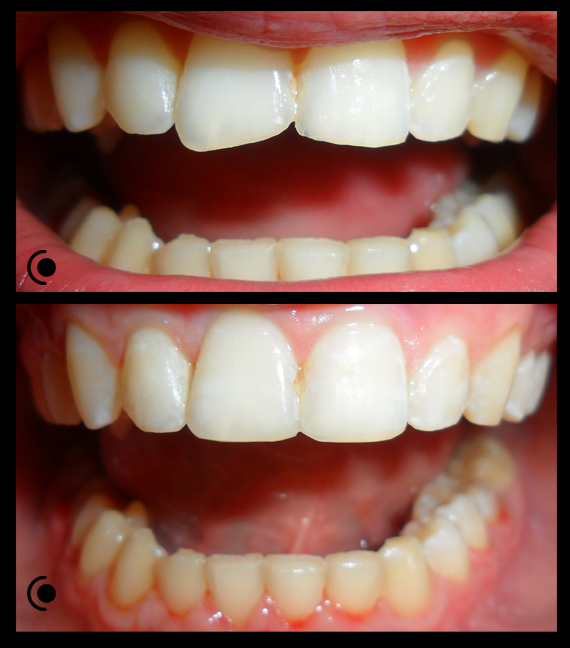

O našoj kvaliteti najbolje govore naši rezultati!

Centar za ortodonciju Petra Džapo